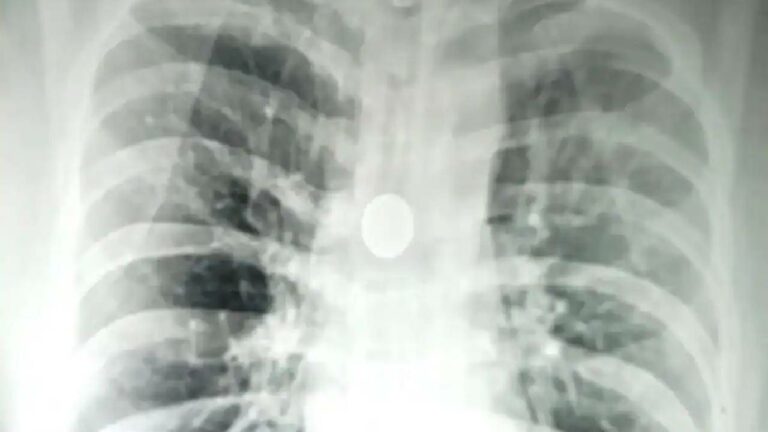

Coin Stuck In Man's Windpipe: బనారస్ హిందూ యూనివర్సిటీ(బీహెచ్‌యూ)లోని శ్రీ సుందర్‌లాల్ హాస్పిటర్‌లో అరుదైన శస్త్రచికిత్స జరిగింది. 8 ఏళ్లుగా 40 ఏళ్ల వ్యక్తి శ్వాసనాళంలో ఇరుక్కుపోయిన 25 పైసల నాణేన్ని తొలగించారు.